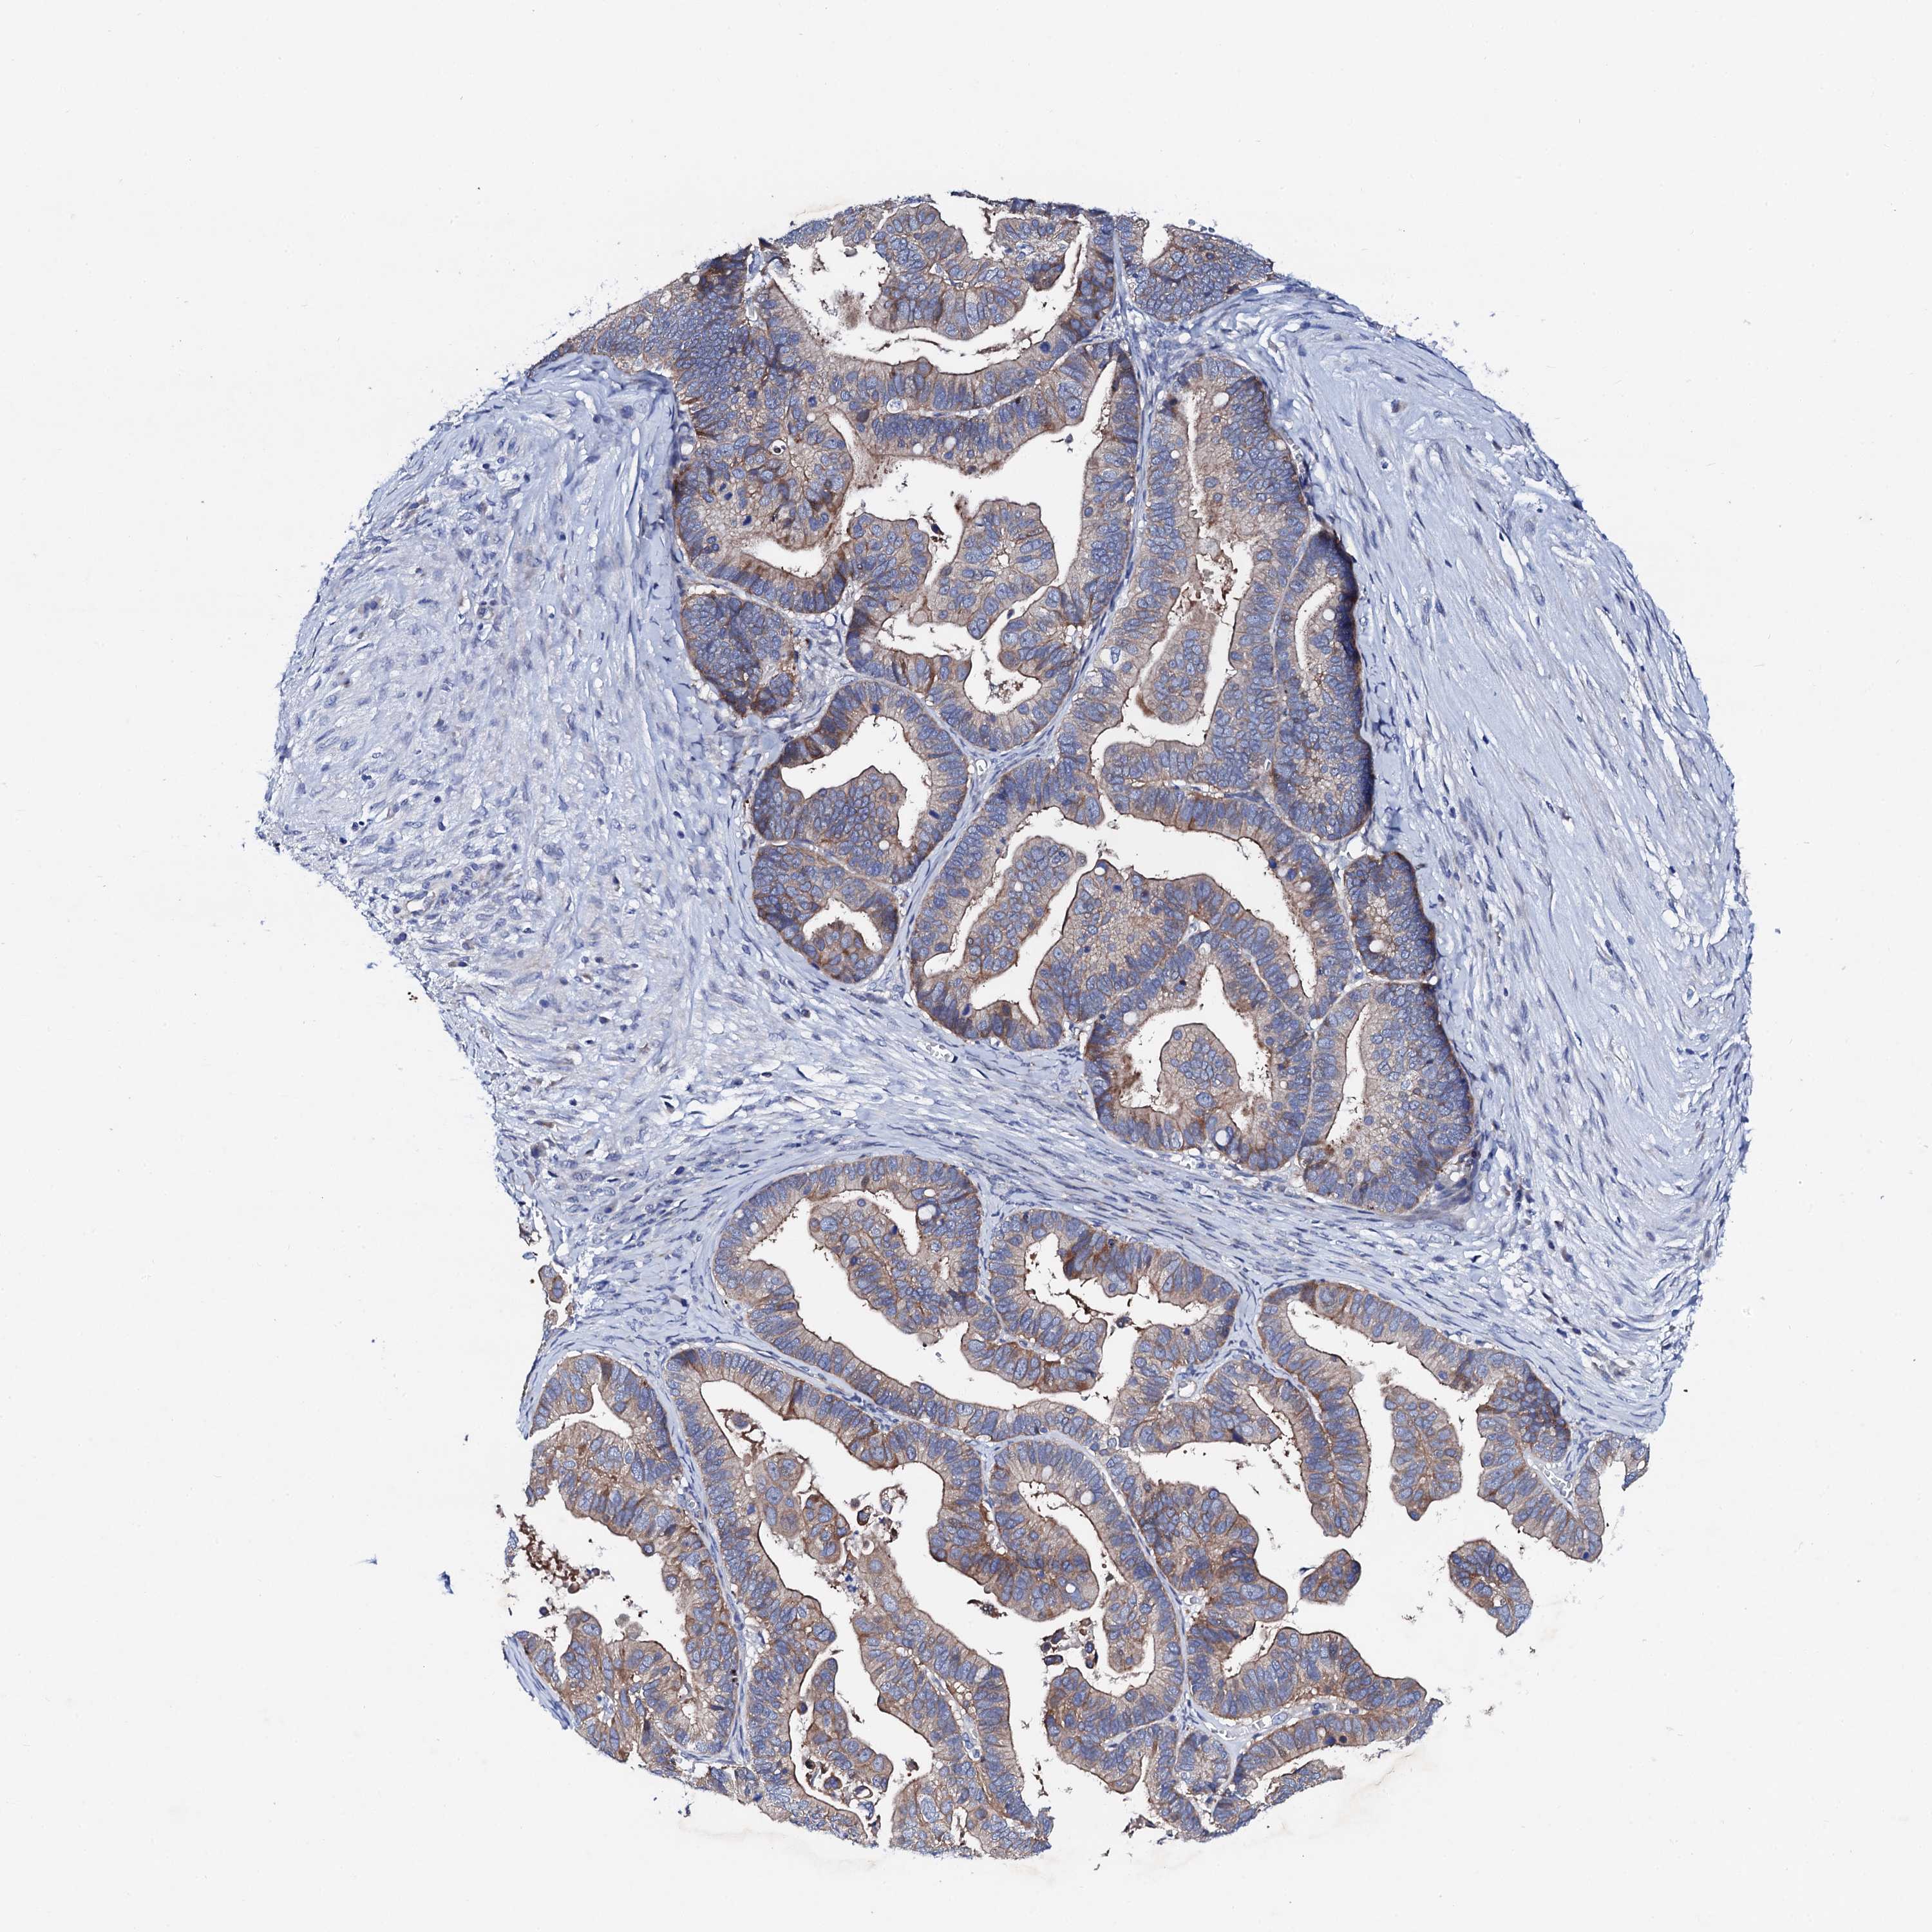

OVARIAN CANCER - Protein expressioni

A mouse-over function shows sample information and annotation data. Click on an image to view it in a full screen mode. Samples can be filtered based on level of antibody staining by selecting one or several of the following categories: high, medium, low and not detected. The assay and annotation is described here.

Note that samples used for immunohistochemistry by the Human Protein Atlas do not correspond to samples in the TCGA dataset.

Antibody stainingi

Antibody staining in the annotated cell types in the current human tissue is reported as not detected, low, medium, or high, based on conventional immunohistochemistry profiling in selected tissues. This score is based on the combination of the staining intensity and fraction of stained cells.

Each image is clickable and will lead to virtual microscopy that enables deeper exploration of all samples and also displays staining intensity scores, fraction scores and subcellular localization as well as patient and tissue information for each sample.

Antibody HPA038226

Antibody HPA058226

Staining

High

Medium

Low

Not detected

Intensity

Strong

Moderate

Weak

Negative

Quantity

>75%

75%-25%

<25%

None

Location

Nuclear

Cytoplasmic/membranous

Cytoplasmic/membranous,nuclear

Cystadenocarcinoma, serous, NOS

Carcinoma, endometroid

Cystadenocarcinoma, mucinous, NOS

Carcinoma, NOS